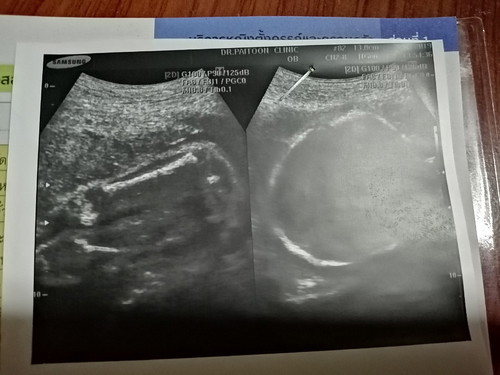

แบบนี้ผู้หญิงหรือผู้ชายค่ะ

น้องไม่อ้าเดายากจังค่ะ